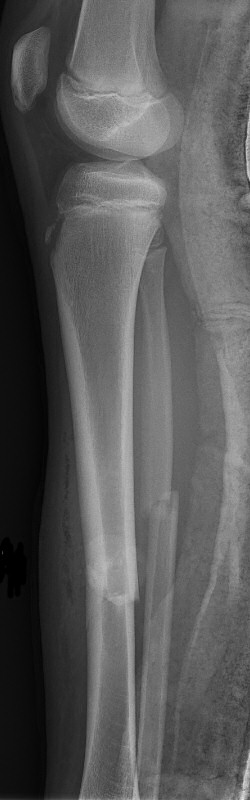

Tibia och fibula-frakturer, tibia spikats med 2 TEN-spik, sista 2 bilderna efter 5 veckor, då inte alls ömmande över frakturerna.